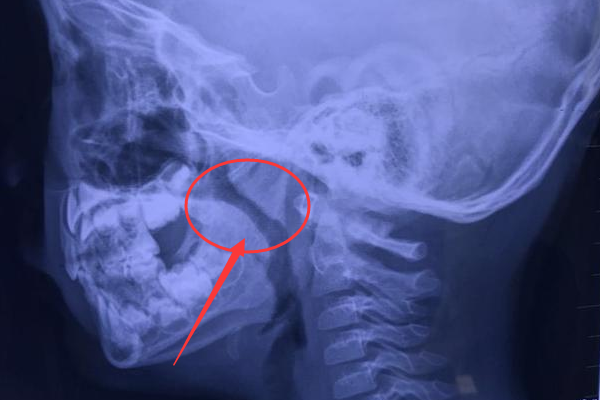

腺样体肥大的诊断及测量标准?

昨天带弟弟去拍ct,确实是腺样体肥大